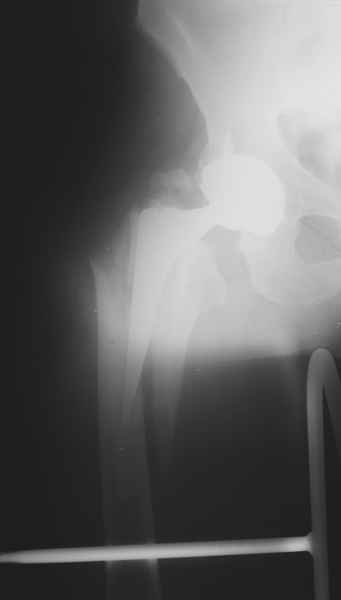

Весь проксимальный отдел бедренной кости ведь смещен относительно ножки эндопротеза? Значит менять ножку нужно. К тому же, если думать об удлинении ножки стержнем, место стыка получится как раз в области поперечной части перелома и о стабильности такой конструкции вряд ли можно будет думать. Так что - длинная ревизионная ножка с остеосинтезом. Может быть и серкляжей будет достаточно если перелом проксимальной части не оскольчатый (по снимкам не очень понятно).

Начинать, на мой взгляд, надо с того, что перелом-то произошел из-за порочной (варусной) позиции ножки, не случись он сейчас, это произошло бы еще через полгода при более невинных обстоятельствах. Не видел конструкций , но дизайн ножки сильно напоминает цементную стандартную ножку Мюллера и, стало быть, наверное есть цементная мантия. В любом случае, на реинтеграцию этой ножки расчитывать нельзя. Поэтому, если нет общесоматических противопоказаний, нужно выполнять ревизионное эндопротезирование, оптимальный вариант - ножка Wagner Cone.

Это"Corail", так что никакой цементной мантии там нет.Непонятно с чего Вы решили,что ножка была установлена в "варусе"? Нынешнее ее положение, получено после травмы.

Частично правильный ответ - 1. Это В-2 перелом (проксимальный отдел скорее жив, чем мертв). Костная пластика кортикальными трансплантатами необходима. Также необходим остеосинтез большим количеством проволочных металлических серкляжей. Пластина не нужна.

Используя ножку "Вагнер", как советует Рашид Муртазалиевич получите хорошую фиксацию по каналу, качественную адаптацию отломков, экономию финансов.

Произведено закрытое удлинение ножки эндопротеза с помощью ретроградного интрамедуллярного стержня. Продолжительность операции 3 часа. Два из них закрытое восстановление длины бедра диистрактором

Пациента удалось осмотреть недавно. Достигнутый результат сохраняется. Перелом бедра сросся. Конечность опорная и безболезненная, ходит без трости. Ножка, похоже, реинтегрировалась, как и надеялись. Снимки и фото в приложении. Комментарии приветствуются.

Надо ли что-то делать дальше, как полагаете? Убрать винты? Убрать "удлинитель ножки"? Или оставить все, как есть? Спасибо заранее.